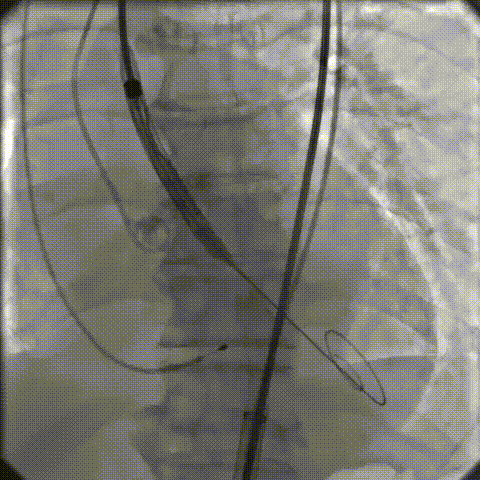

手术影像记录

主动脉根部造影

18mm球囊预扩

AV26瓣膜工作位造影

缓慢脱钩

23mm球囊后扩

后扩后造影:无漏

术中剪影